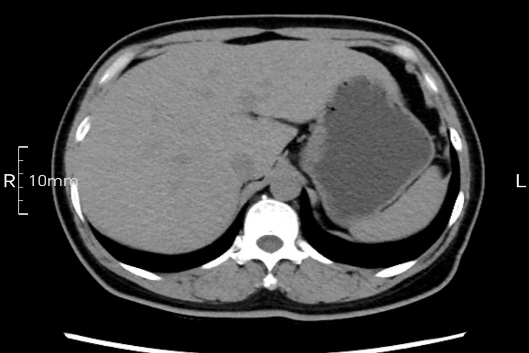

看看下面三幅便知遵醫(yī)囑的重要性。

沒禁食,胃內(nèi)全是食物,導(dǎo)致胃壁顯示不清。

禁食但檢查前沒有喝飽,胃未能漲開,胃壁觀察效果不佳。

完美禁食且喝飽飽,胃壁完美展現(xiàn)。